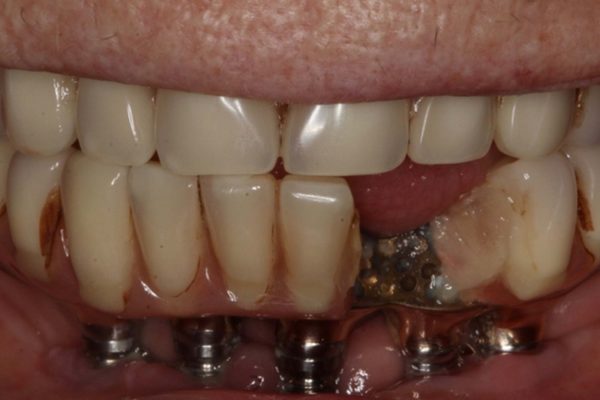

Figures 1-3 show a 90-year-old patient, who presented with a fractured 26-year-old implant bridge. This bridge has been in place for 24 years without incident. The patient was very happy with it.

Approximately two years ago some of the teeth fractured off. An intra-oral repair was carried out by the patient’s GDP. The patient was generally happy with this but always felt this area was a bit delicate.

From my discussion with the patient, along with my assessment and radiograph (shown in Figure 4) I was able to find out this patient had been treated with Branemark implants, and the restoration was an acrylic bridge with a gold framework.